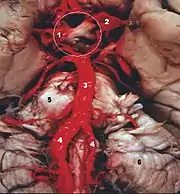

Anatomía

El sistema vertebrobasilar o VBS es el único en la anatomía humana, en que dos arterias diferentes se fusionan en una arteria única. Este sistema arterial provee la circulación del encéfalo posterior.[2]

Las dos arterias vertebrales y la arteria basilar proporcionan sangre a la parte posterior del círculo arterial cerebral y se anastomosa con la parte anterior del círculo, irrigado por las arterias carótidas.